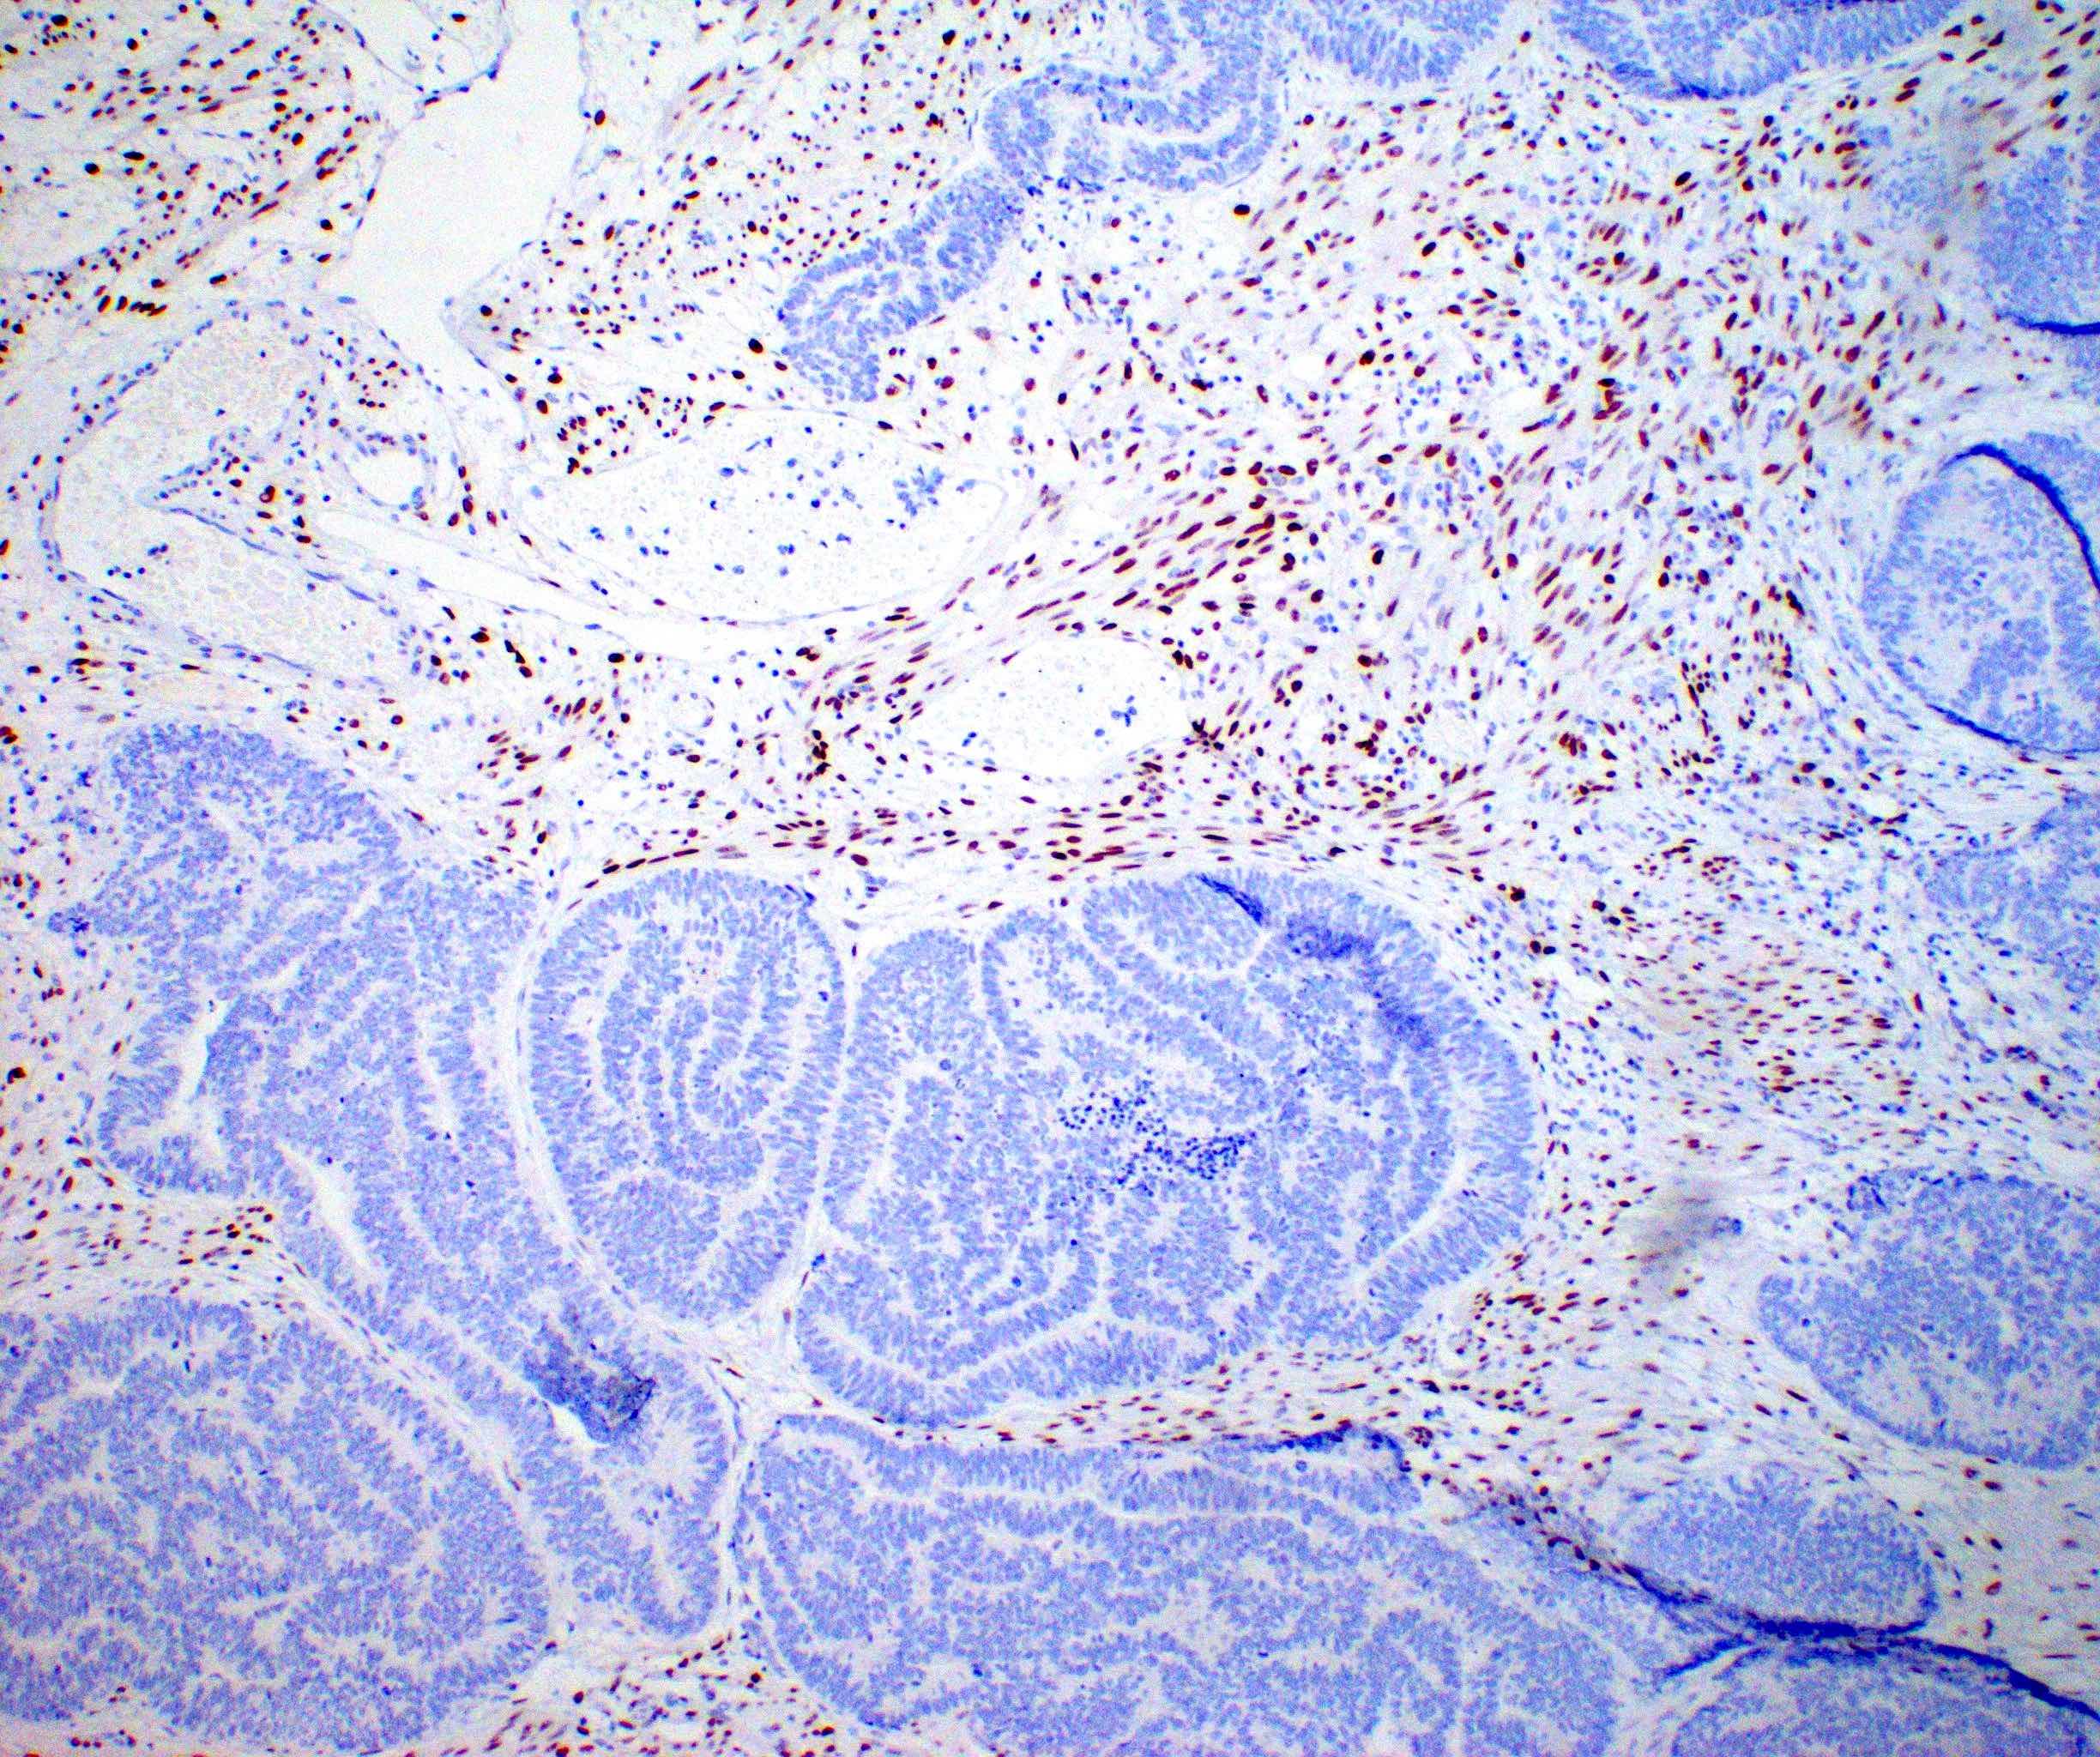

Microscopic (histologic) images

Contributed by Daniel Graham, M.D., Adele Wong, M.B., B.Ch., B.A.O. and Lucy Ma, M.D.

Positive stains

- PAX8: usually diffusely positive

- GATA3 and TTF1: focal or diffuse with inverse staining pattern described in several studies in the most recent WHO classification; cells positive for GATA3 are negative for TTF1 and vice versa (Am J Surg Pathol 2018;42:1596)

- CD10: focal and apical / luminal

- p53 wild type

- MMR proficient

Negative stains

- ER

- PR (more reliable negative marker than ER)

- Calretinin (usually negative may be focally positive)